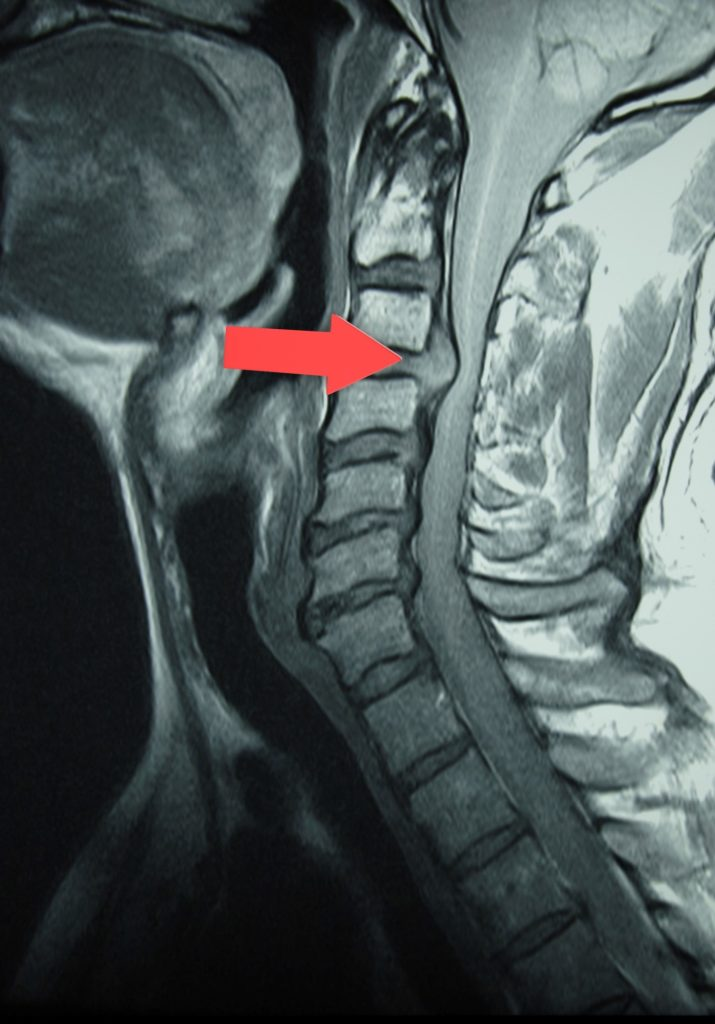

Nekhernia, de uitstulping van de tussenwervelschijf duwt tegen de zenuw aan de achterzijde. Dit geeft uitstraling in de arm en hand.

Onze fysiotherapeut kan de diagnose stellen door een aantal testen uit te voeren. Bij verdenking op een nekhernia kunnen we u doorsturen voor verder beeldvormend onderzoek. Röntgenfoto’s bieden meestal weinig informatie en worden slechts gebruikt om andere mogelijke bronnen van pijn uit te sluiten. Bij twijfel over de diagnose kan een MRI worden gemaakt..